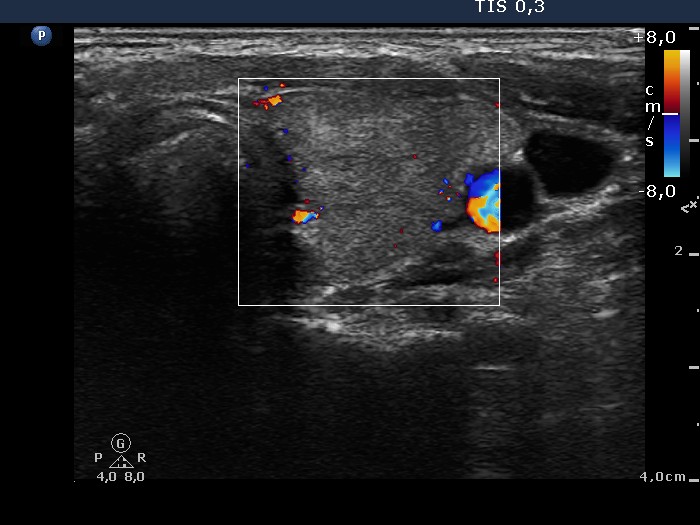

Graves' disease - Case 1049

Follow-up investigation 36 months after first visit (ultrasonographic picture 6)

Patient on daily 10 mg methimazole therapy in euthyroid state

Left lobe, transverse scan, color Doppler mode. The vascularization is practically absent.